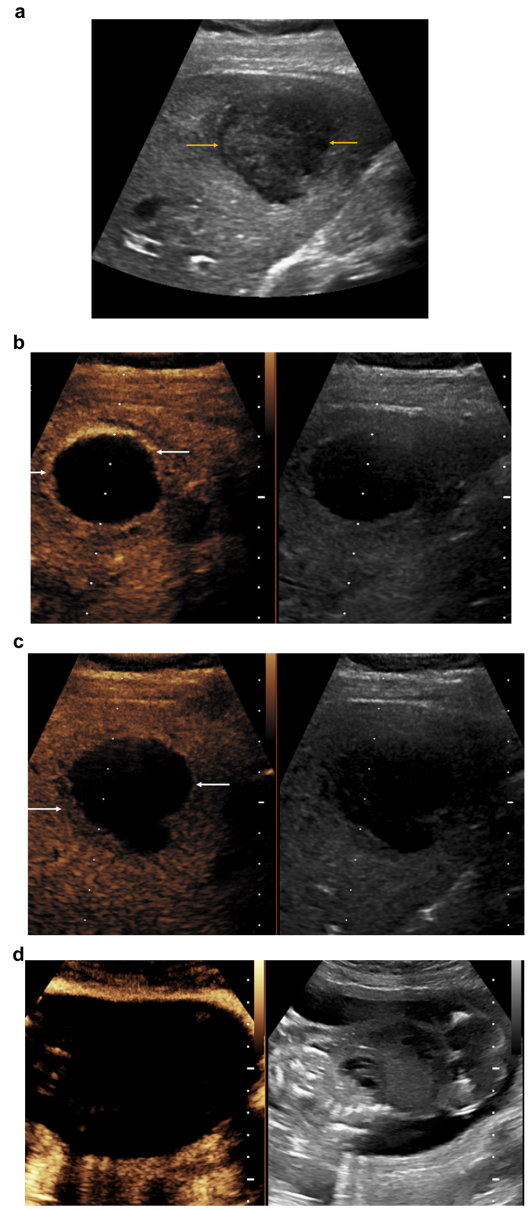

数据显示微泡造影剂无法穿透胎盘屏障,妊娠期CEUS诊断肝脓肿、胎盘植入时胎儿均无显影。相比存在钆沉积风险的MRI,CEUS在29岁孕妇肝脓肿案例中精准显示病灶周边强化,而妊娠囊始终保持无增强状态

儿科实践:儿童友好型影像革命

FDA已批准LumasonTM用于儿童肝病变诊断。14岁自身免疫性肝炎患儿通过CEUS明确12mm病灶为良性局灶性结节增生(FNH),动脉期"轮辐状"强化模式清晰可见